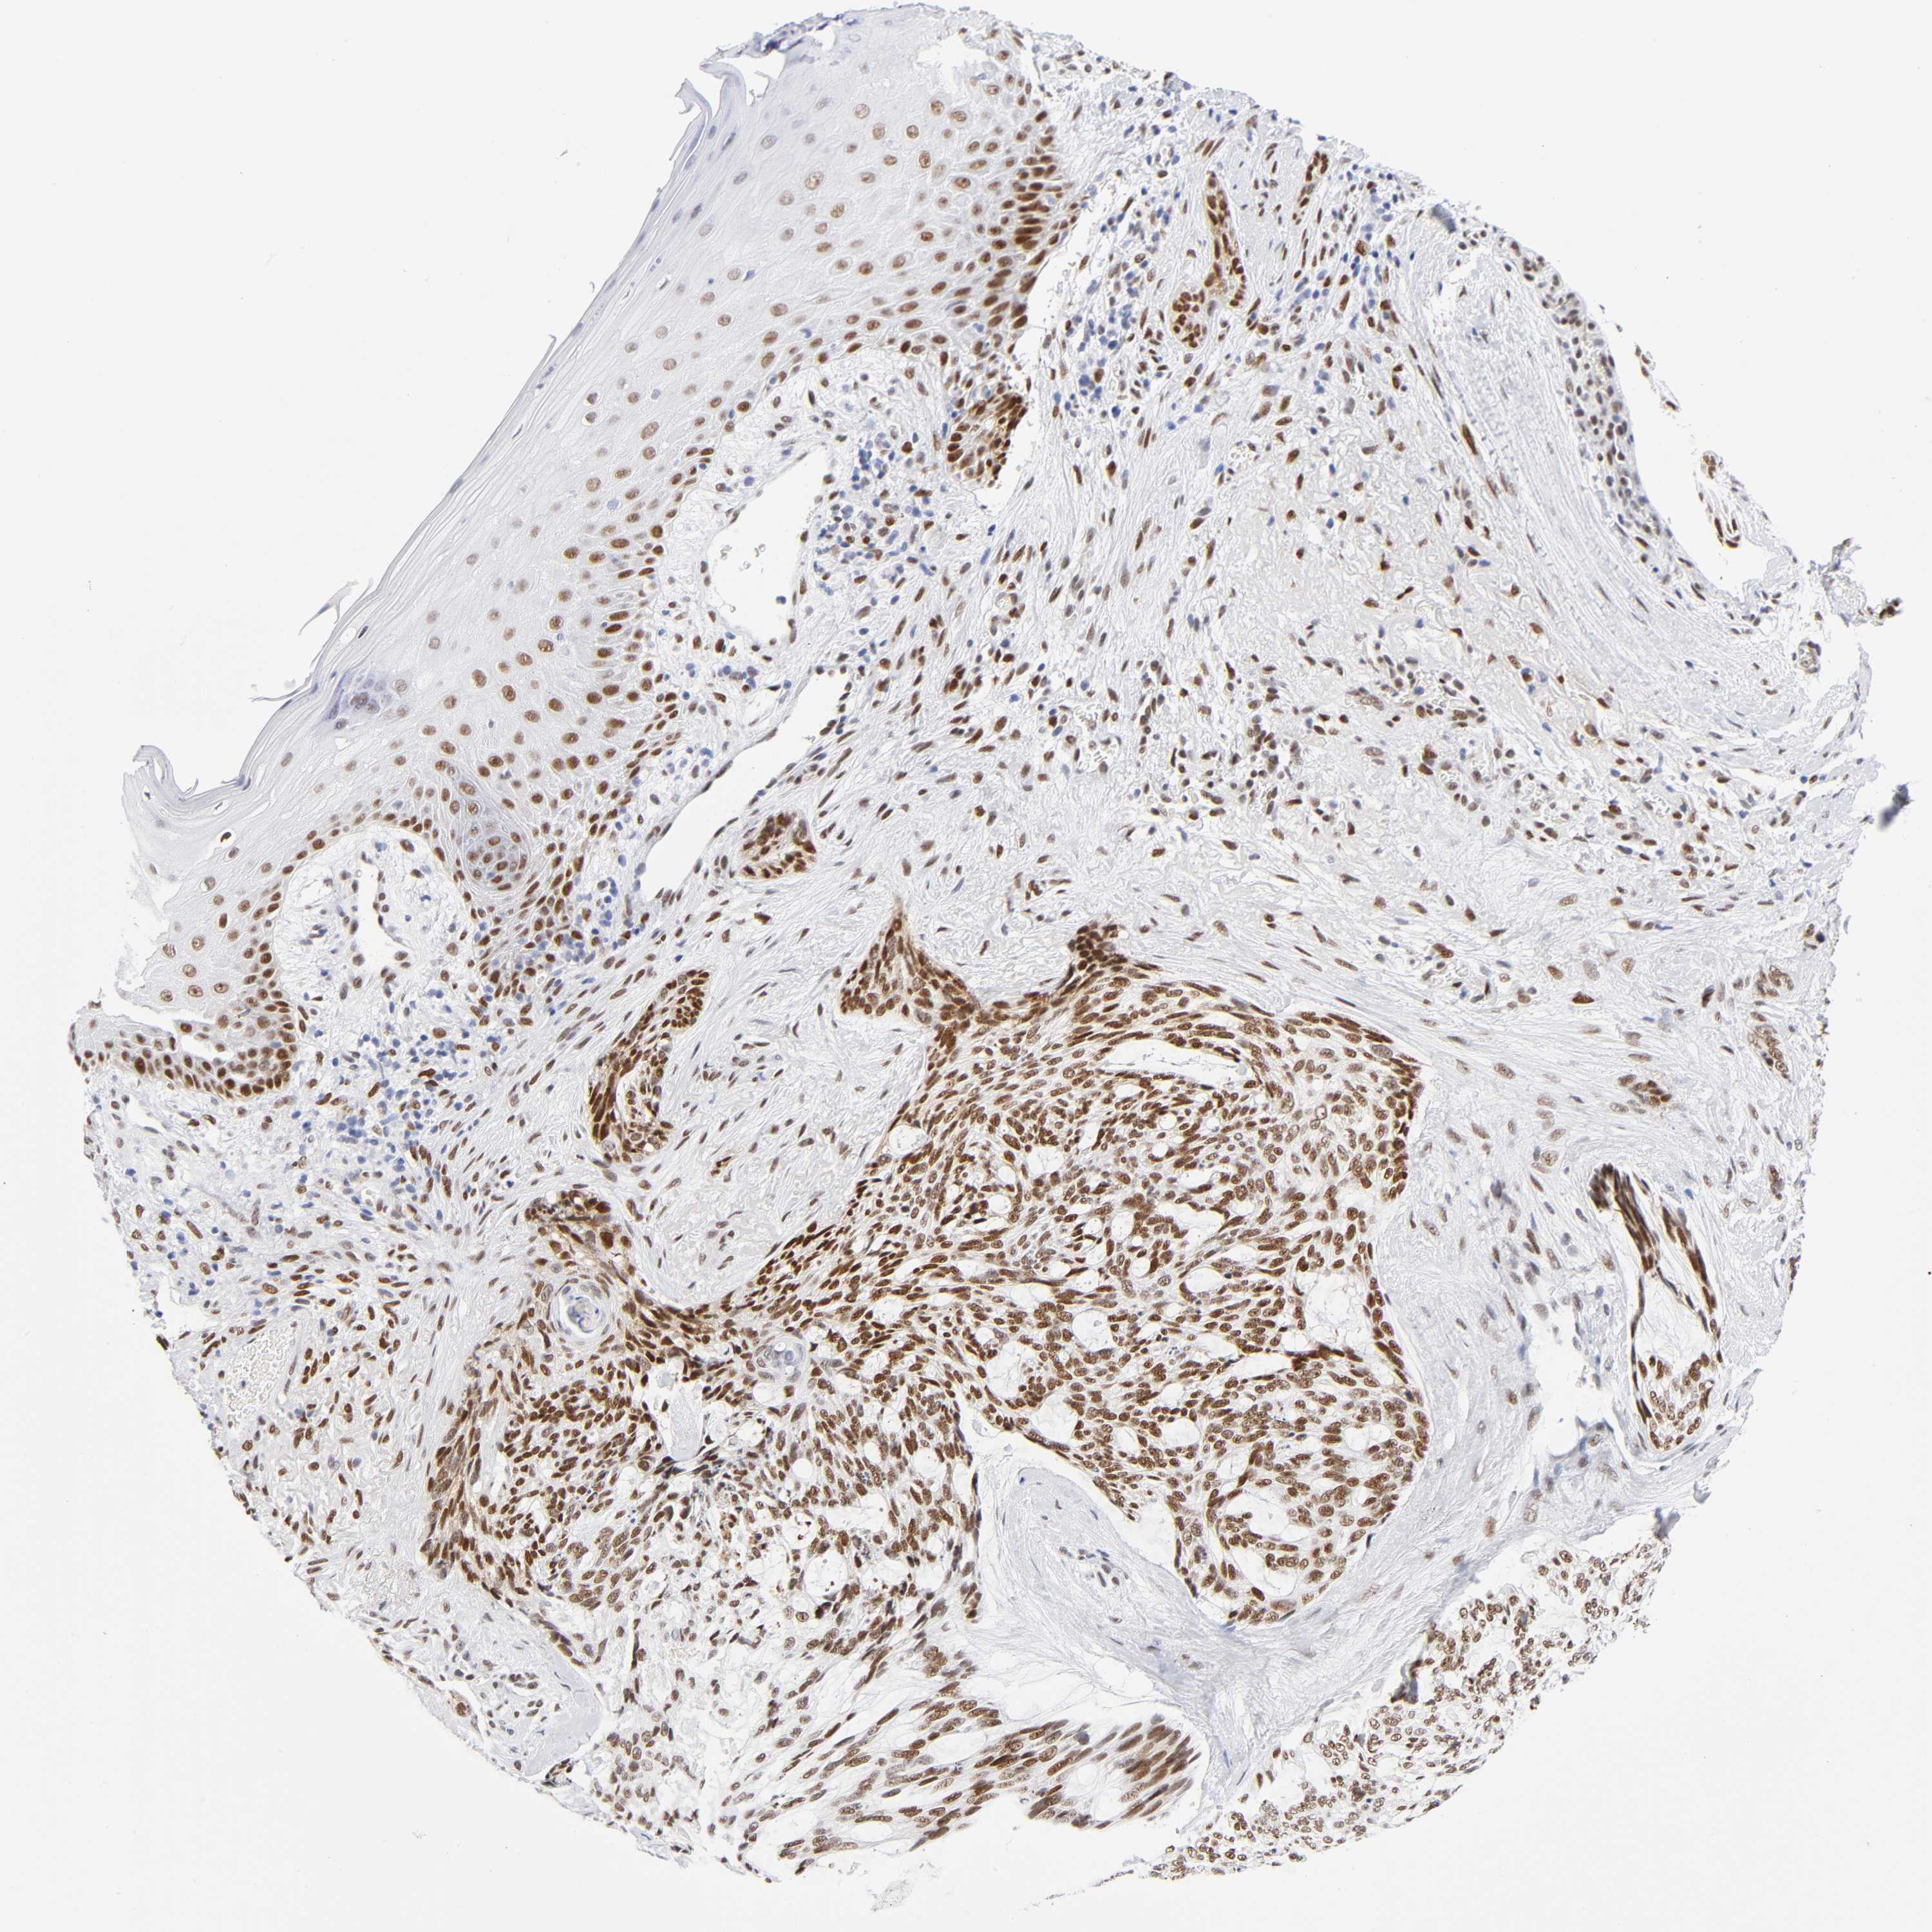

SKIN CANCER - Protein expressioni

A mouse-over function shows sample information and annotation data. Click on an image to view it in a full screen mode. Samples can be filtered based on level of antibody staining by selecting one or several of the following categories: high, medium, low and not detected. The assay and annotation is described here.

Antibody staining in the annotated cell types in the current human tissue is reported as not detected, low, medium, or high, based on conventional immunohistochemistry profiling in selected tissues. This score is based on the combination of the staining intensity and fraction of stained cells.

Each image is clickable and will lead to virtual microscopy that enables deeper exploration of all samples and also displays staining intensity scores, fraction scores and subcellular localization as well as patient and tissue information for each sample.

Antibody CAB004674

Staining

High

Strong

>75%

Location

Basal cell carcinoma

BCC, low aggressive

Squamous cell carcinoma, NOS